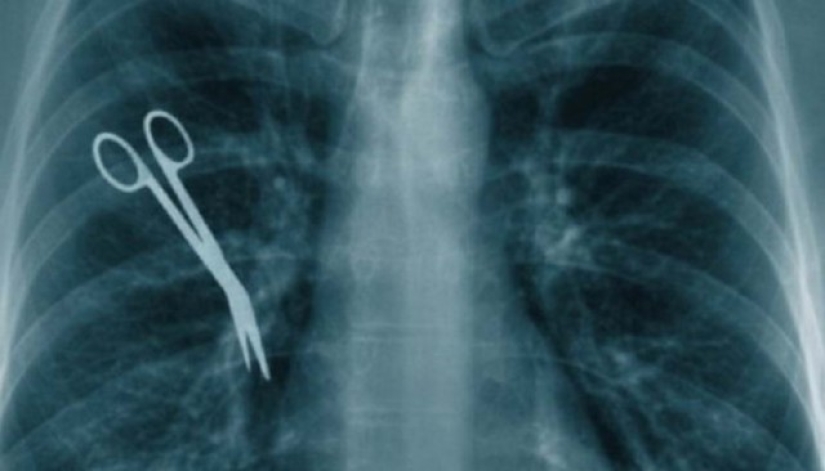

8. Dejar instrumentos quirúrgicos dentro del paciente.

Realmente quiero creer que esto es un mito. Pero, de hecho, esto no sucede tan raramente. Fórceps, bisturíes, tijeras e incluso instrumentos más imponentes se olvidan en los pacientes. Lo peor de todo es que es posible que el artículo abandonado no se muestre en absoluto durante años.